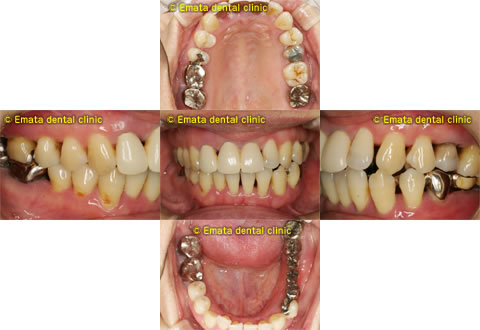

歯周再生・歯列補正・審美補綴まで一口腔単位で整えた包括治療

歯周再生療法 歯周矯正治療 ジルコニアセラミック治療

Before

After

| 主訴 | 歯がぐらぐらする。歯周病を治したい。 |

|---|---|

| 治療期間・回数 | 約2年・約15回 |

| 費用 | 2,300,000円 |

| デメリット・注意点 | 詰め物・被せ物の調整が難しく、割れた場合は再治療が必要。 |